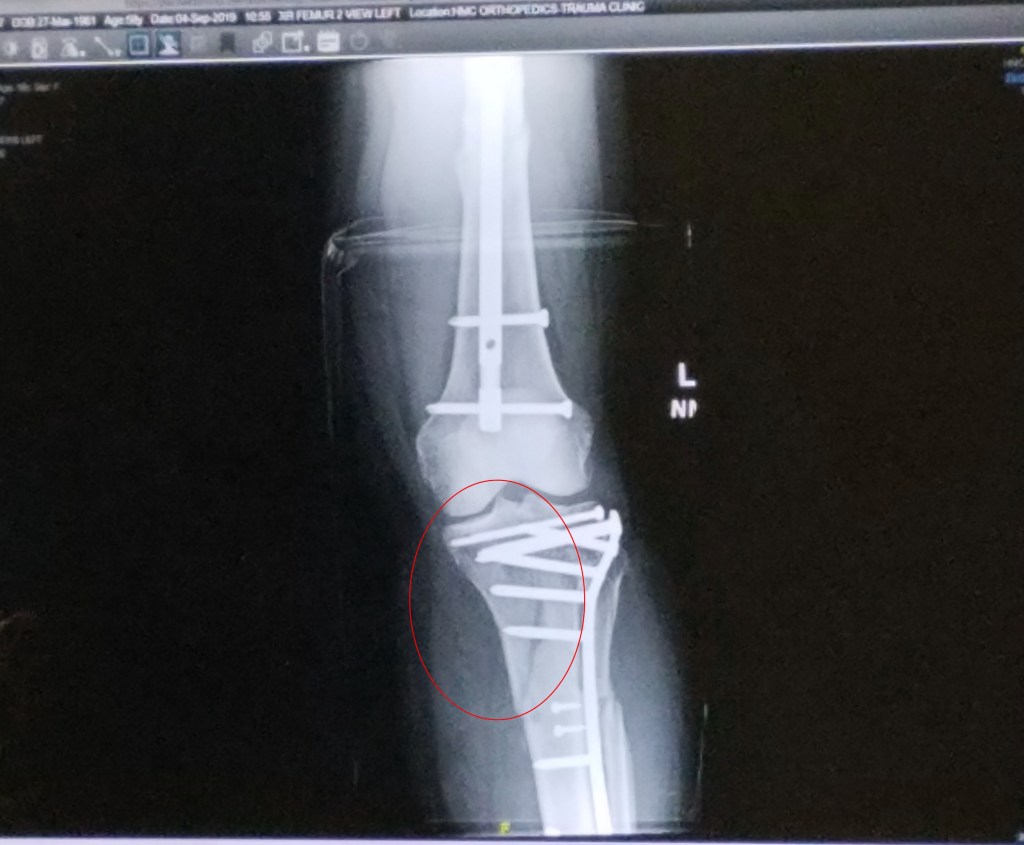

Zooming in on this week’s x-rays, I can see the top half of my tibia was completely separated. And I know the large puncture wound on the front of my shin was the result of the bone poking through the skin. I want to trust the plate and ten pins along with the three long screws holding it together, but it’s difficult, seeing the extent of the break.

Below this plate “assembly” are two more plates with their own collection of 13 pins and screws. Altogether, my badly mangled tibia is held together with 3 plates, and 25 pins and screws. My fibula, which was snapped in half, wasn’t fixed, and is somewhat knitted together. Supposedly, it’s not weight bearing.

At the top of my femur are three huge screws and running the length of the femur is a rod, secured with a couple of pins. I’m confident with the repair of my femur.

Until Wednesday, I pretended to “see” the x-rays. This week, I snapped pictures with my smart phone to better understand what comprises the erector set, which is the superstructure now holding my leg together. Maybe denial was healthier. I could amuse myself with the fantasy that starting to walk was going to be a breeze.